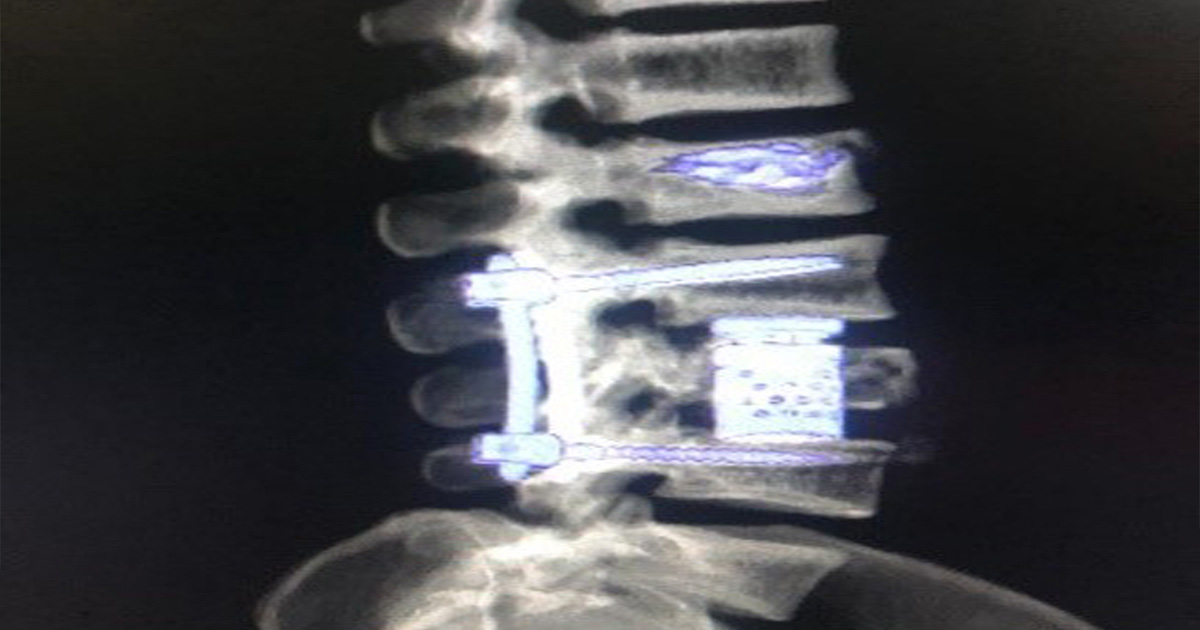

Por lo cual a este paciente de 25 años se realiza procedimiento quirúrgico donde la junta médica definió y se autoriza colocación en decúbito lateral N bloque para evitar úlceras por presión. Además, se hace restauración anatómica por distracción intravertebral de L1, fijación transpedicular de L2-L4 percutánea, vertebrectomia de L3 vía anterolateral con colocación de cilindro expandible. Por último, neurocirugía por artrodesis L2-L4 posterior más corpectomia anterior de L3 más restauración anatómica de L1.